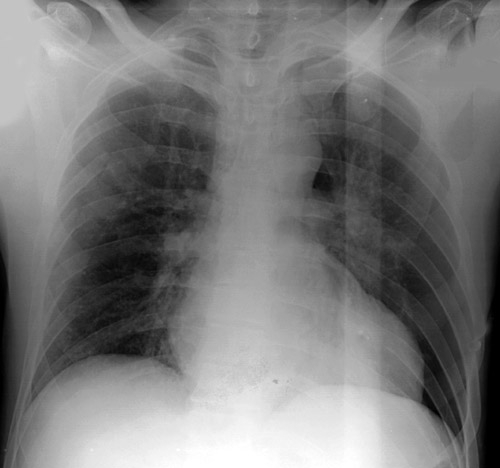

Now look at the following radiograph. Can you find the rib fracture? The hematoma on the patient's left side should be a hint.

AP view of chest